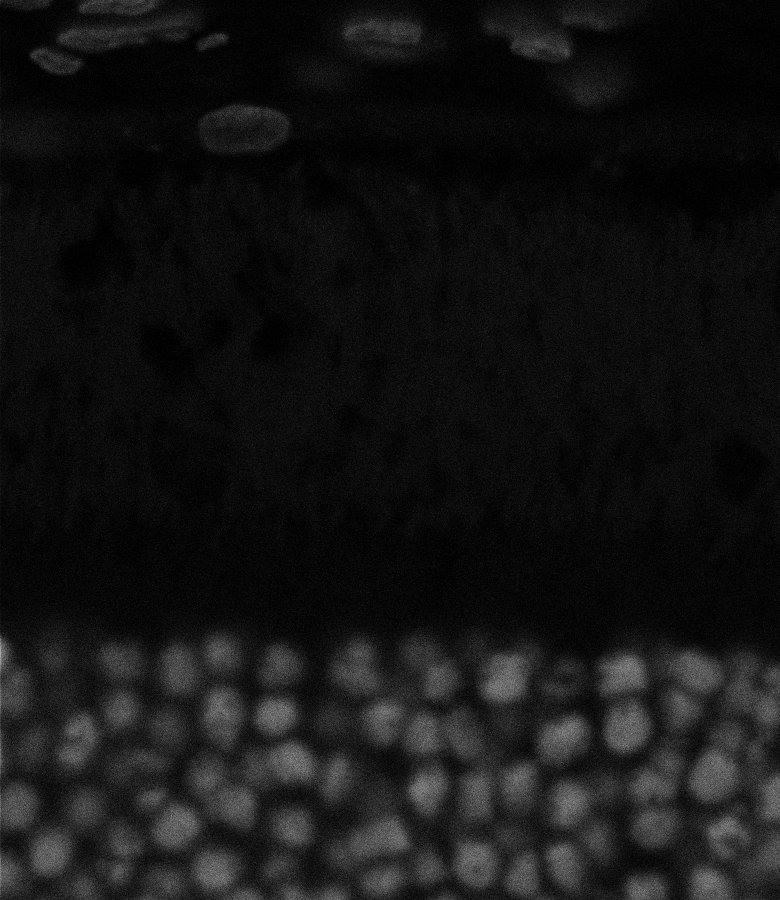

Nuclei

Nuclei - Bis

Nuclei - Bip

Nuclei - Bipolar